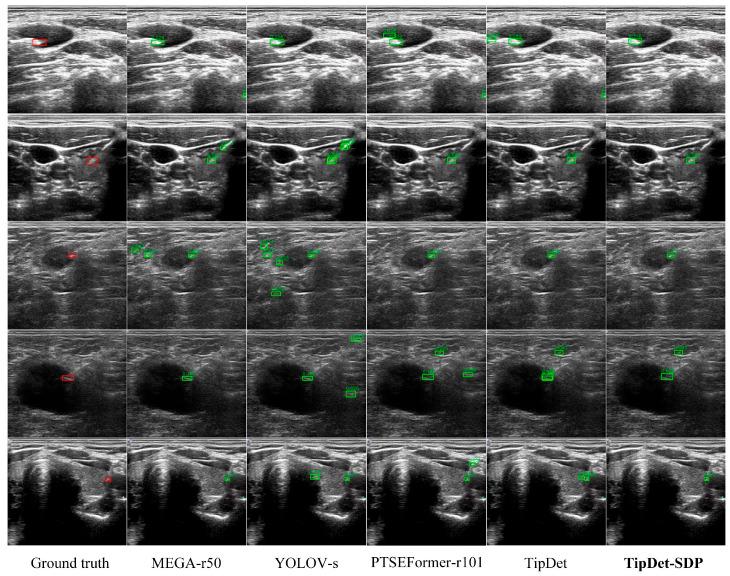

: Automatic tip localization is critical in ultrasound (US)-guided interventions. Although deep learning (DL) has been widely used for precise tip detection, existing methods are limited by the availability of real puncture data and expert annotations. : To address these challenges, we propose a novel method that uses synthetic US puncture data to pre-train DL-based tip detectors, improving their generalization. Synthetic data are generated by fusing clinical US images of healthy controls with tips created using generative DL models. To ensure clinical diversity, we constructed a dataset from scans of 20 volunteers, covering 20 organs or anatomical regions, obtained with six different US machines and performed by three physicians with varying expertise levels. Tip diversity is introduced by generating a wide range of synthetic tips using a denoising probabilistic diffusion model (DDPM). This method synthesizes a large volume of diverse US puncture data, which are used to pre-train tip detectors, followed by subsequently training with real puncture data. : Our method outperforms MSCOCO pre-training on a clinical puncture dataset, achieving a 1.27-7.19% improvement in AP with varying numbers of real samples. State-of-the-art detectors also show performance gains of 1.14-1.76% when applying the proposed method. The experimental results demonstrate that our method enhances the generalization of tip detectors without relying on expert annotations or large amounts of real data, offering significant potential for more accurate visual guidance during US-guided interventions and broader clinical applications.

自动针尖定位在超声(US)引导介入中至关重要。尽管深度学习(DL)已被广泛用于精确的针尖检测,但现有方法受到真实穿刺数据和专家标注可用性的限制。为应对这些挑战,我们提出了一种新颖的方法,该方法使用合成的US穿刺数据对基于DL的针尖探测器进行预训练,以提高其泛化能力。合成数据是通过将健康对照的临床US图像与使用生成式DL模型创建的针尖融合而生成的。为确保临床多样性,我们从20名志愿者的扫描中构建了一个数据集,涵盖20个器官或解剖区域,使用六台不同的US机器获取,并由三名专业水平不同的医生进行操作。通过使用去噪概率扩散模型(DDPM)生成广泛的合成针尖来引入针尖多样性。该方法合成了大量多样的US穿刺数据,用于预训练针尖探测器,随后再用真实穿刺数据进行训练。我们的方法在临床穿刺数据集上优于MSCOCO预训练,在不同数量的真实样本下,平均精度(AP)提高了1.27 - 7.19%。当应用所提出的方法时,最先进的探测器也显示出1.14 - 1.76%的性能提升。实验结果表明,我们的方法在不依赖专家标注或大量真实数据的情况下增强了针尖探测器的泛化能力,为US引导介入期间更准确的视觉引导和更广泛的临床应用提供了巨大潜力。